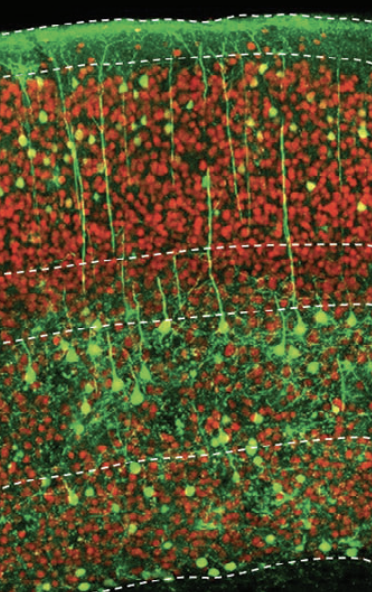

NeuExcell利用安全高效的递送载体如AAV,通过表达NeuroD1等神经转录因子,在不同脑区将胶质细胞原位转分化位不同类型神经元,从而实现原位神经再生。原位转分化技术可应用于多种罕见和常见的神经疾病,且具有安全、可大规模生产的优势。